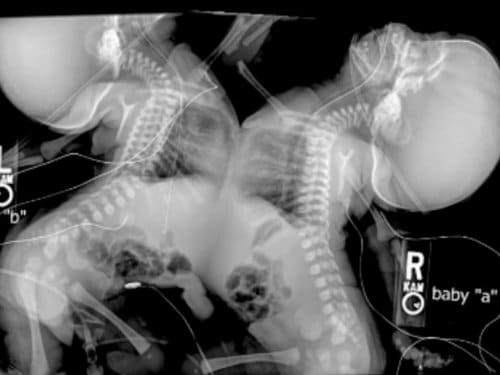

En un ecosonograma, parte de su control mensual de rutina, su médico descubrió que los mellizos, tenían una particularidad, estaban unidos por el tórax, es decir, eran siameses. Con nulas esperanzas de vida según el diagnóstico médico, el aborto era necesario.